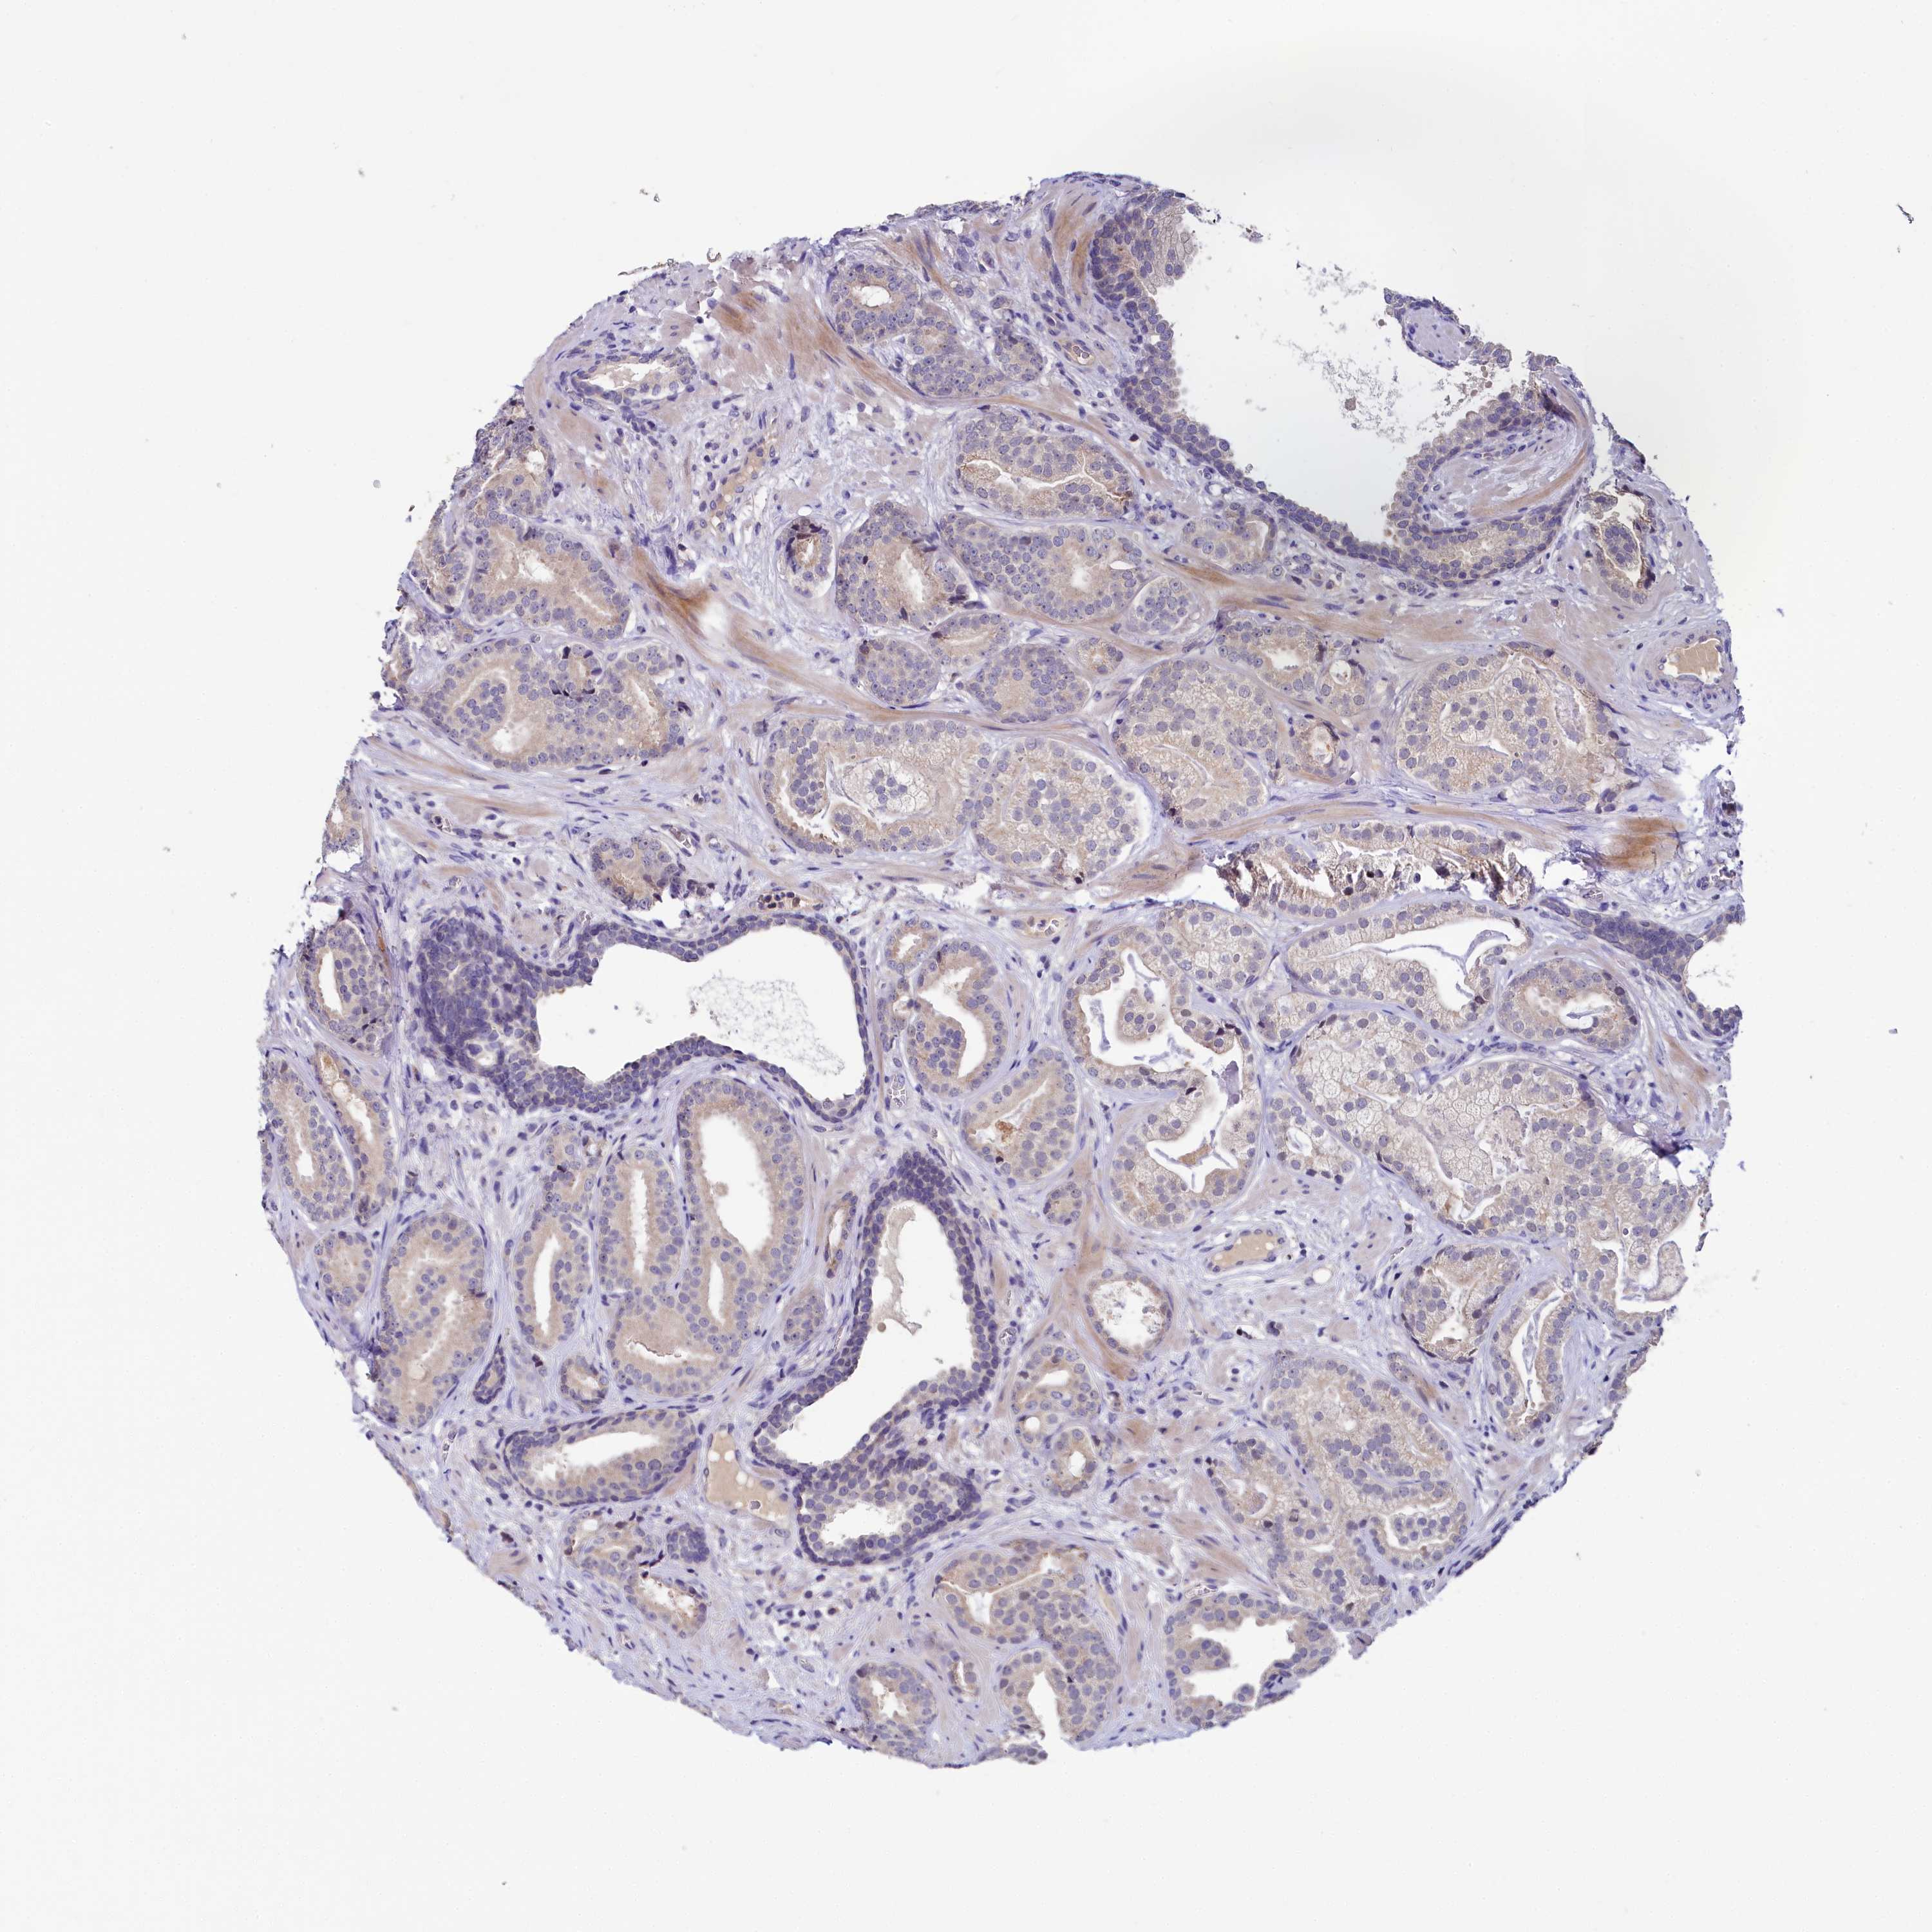

PROSTATE CANCER - Protein expressioni

A mouse-over function shows sample information and annotation data. Click on an image to view it in a full screen mode. Samples can be filtered based on level of antibody staining by selecting one or several of the following categories: high, medium, low and not detected. The assay and annotation is described here.

Note that samples used for immunohistochemistry by the Human Protein Atlas do not correspond to samples in the TCGA dataset.

Antibody stainingi

Antibody staining in the annotated cell types in the current human tissue is reported as not detected, low, medium, or high, based on conventional immunohistochemistry profiling in selected tissues. This score is based on the combination of the staining intensity and fraction of stained cells.

Each image is clickable and will lead to virtual microscopy that enables deeper exploration of all samples and also displays staining intensity scores, fraction scores and subcellular localization as well as patient and tissue information for each sample.

Antibody HPA038288

Staining

High

Medium

Low

Not detected

Intensity

Strong

Moderate

Weak

Negative

Quantity

>75%

75%-25%

<25%

None

Location

Nuclear

Cytoplasmic/membranous

Cytoplasmic/membranous,nuclear

Adenocarcinoma, High grade

Adenocarcinoma, Low grade